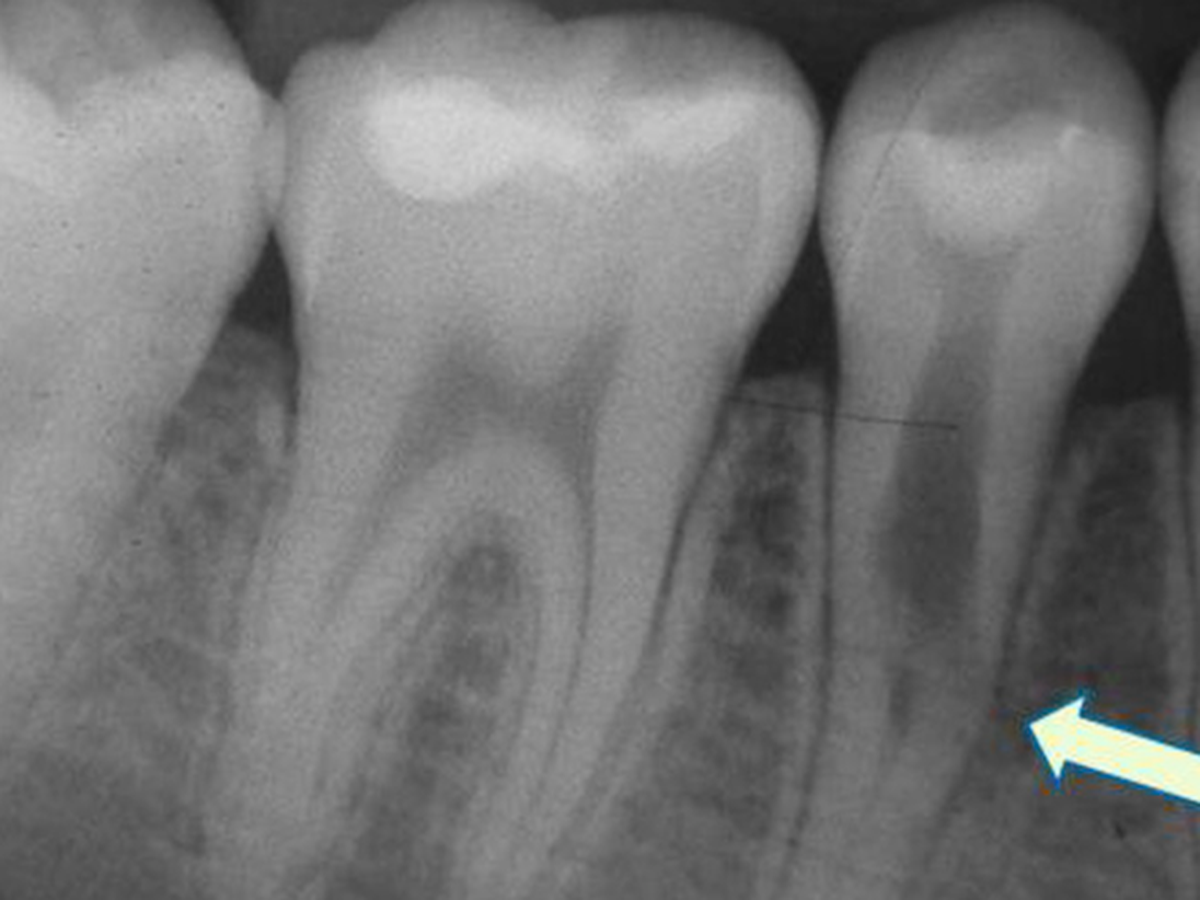

Did you know teeth can just be resorbed? I didn't!

But one of my upper molars, which is super visible when I smile, is being resorbed. Resorption happens more in people who've had orthodontia, and this tooth is one of the ones next to the teeth that got pulled & so would have moved the most when I had braces in Jr High.

NOTE: The tooth image in the header isn't my specific x-ray - I didn't have the foresight to ask for a copy of my x-rays, so I pulled that image from the frankly terrifying amount of x-ray imagery of tooth resorption online.